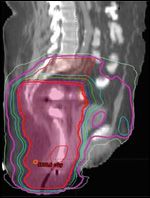

Sagittal image from conventional 3-dimensional radiation planning.FIGURE 5

Sagittal image from intensity- modulated radiation therapy planning in the same patient.FIGURE 6

RTOG 05-29 is a prospective phase II efficacy trial utilizing IMRT in the treatment of anal canal cancer.[39] All patients received concurrent 5FU and MMC. In this study, IMRT was delivered by “dose painting,” in which different target volumes are treated concurrently but different-sized radiation fractions are used for different target structures, which is achievable with IMRT. The doses prescribed to elective nodal areas depended on the stage of disease, and the total dose to gross disease ranged from 50.4 to 54 Gy. As an example, the patient depicted in Figures 2-9 with T2N2M0 disease might have received 1.5 Gy/day (to a total of 45 Gy) to the uninvolved (elective) inguinal and upper pelvic regions, 1.68 Gy/day (to a total of 50.4 Gy) to an involved right pelvic lymph node (which measured ≤ 3 cm), and 1.8 Gy/day (to a total of 54 Gy) to the gross anal canal tumor.